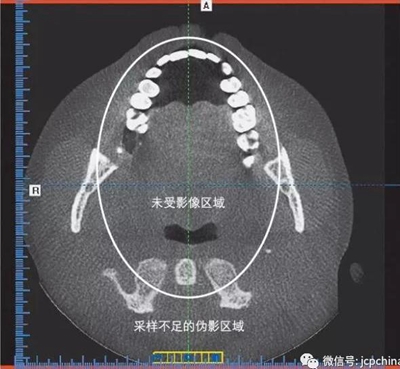

(4)混淆偽影

X線束為錐形的和發(fā)散的,不難看出離放射源最遠(yuǎn)的那部分采樣量不足。采樣不足的偽影顯示為彎曲的紡錘線。偽影在圖像周邊比較明顯,而中央?yún)^(qū)域未受影響。